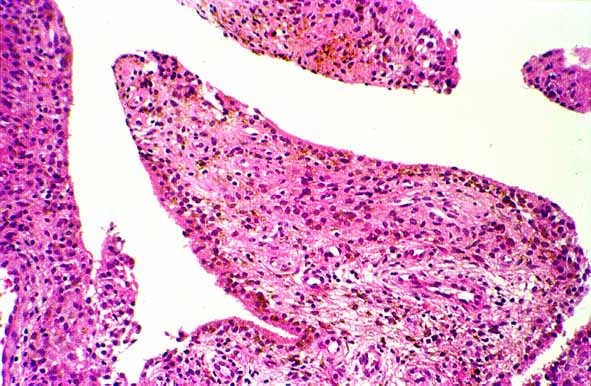

Microscópicamente las delicadas vellosidades están cubiertas por una o varias capas de células sinoviales hipertrofias (figura 7), conteniendo abundante hemosiderina.En el centro de las vellosidades se observan vasos sanguíneos dilatados (figura 8), con un infiltrado linfoplasmocitario (figura 9) y numerosos histiocitos con pigmento hemosiderínico o lípidos ( células espumosas ) (figura 10) y células gigantes multinucleadas en un número variable (figura 11). Estos últimos elementos permiten realizar el diagnóstico diferencial con hemosiderosis sinovial en pacientes con hemofília o con el hemangioma sinovial.